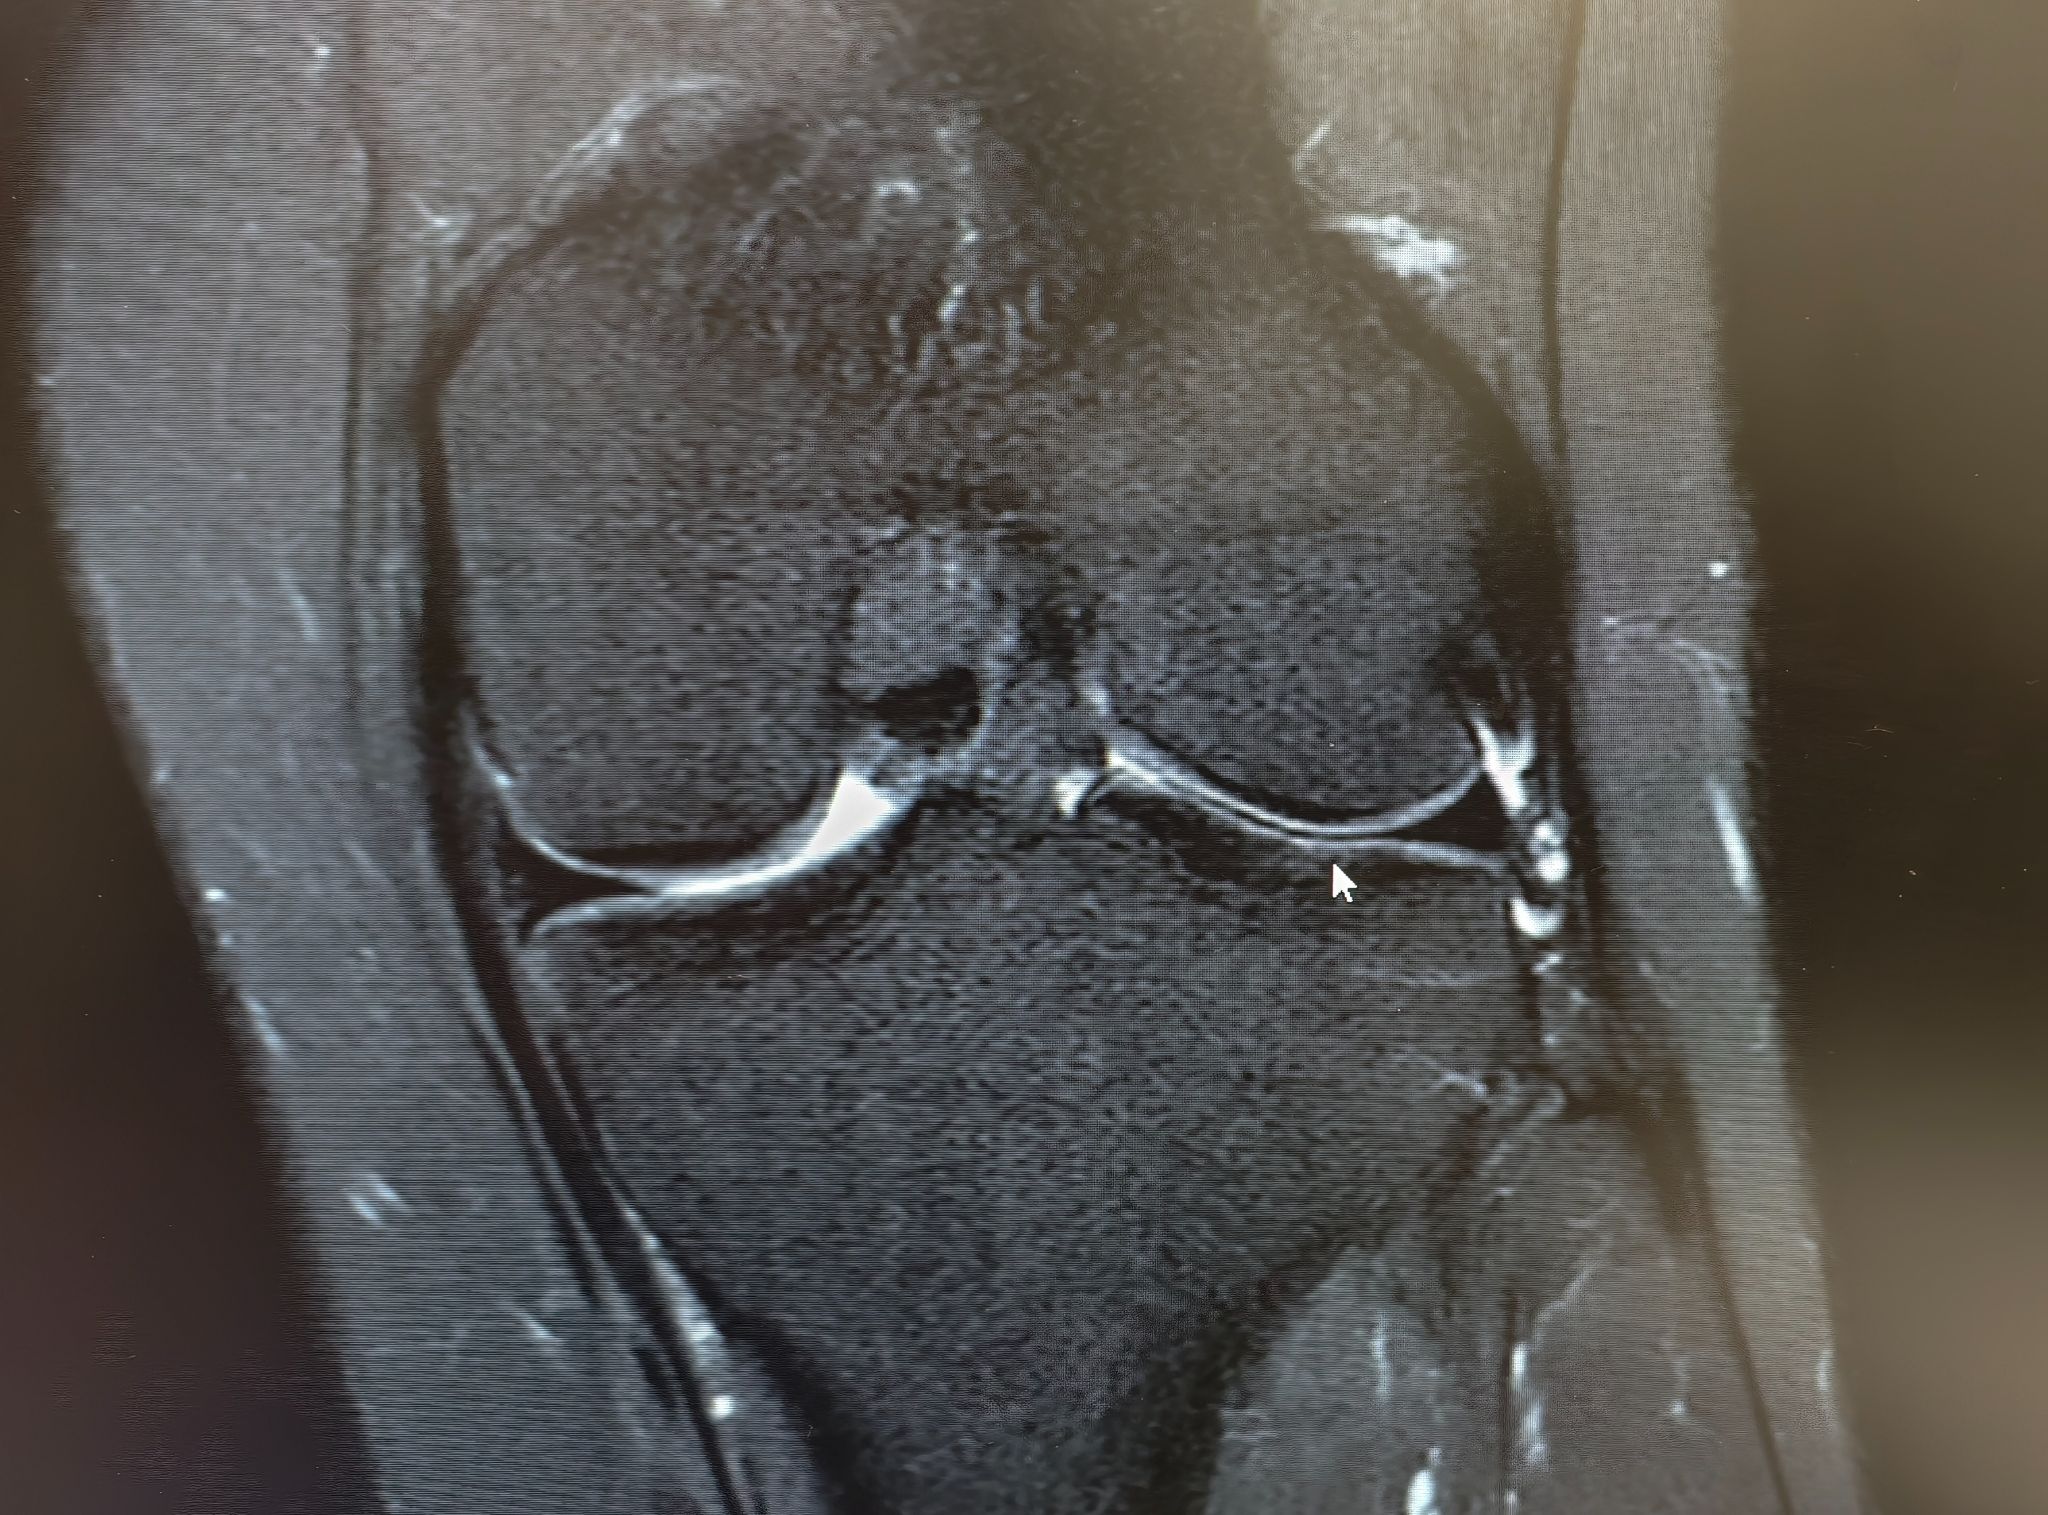

ภาพ mri ประกอบครับ

1. จากภาพประเมินได้เป็นเกรดอะไรบ้างครับ

แพทย์ 2-3 ท่านบอกว่า น่าจะอยู่ที่ระดับ 2 ค่อนไป 3